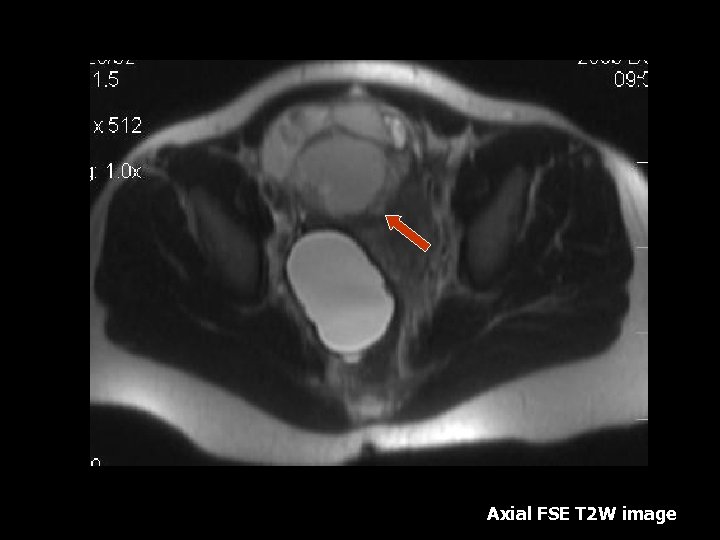

Ovarian Torsion • Fifth most common gynecologic diagnosis(8). • Symptoms – Abdominal pain, nausea and vomiting(8). • Early diagnosis can salvage ovarian function(10%)(8). • Torsion produces circulatory stasis, initially venous, then progresses to arterial(9). • Predisposing factors include ipsilateral adnexal mass, usually benign(9). • Teratoma is the most common benign neoplasm(9).

Torsion • • • MRI findings: Tube thickening(84%) Ovarian cystic mass(76%) Ascites(64%) Deviation of the uterus(36%) Less Common: Hemorrhage and hemoperitoneum

Axial T 1 W image